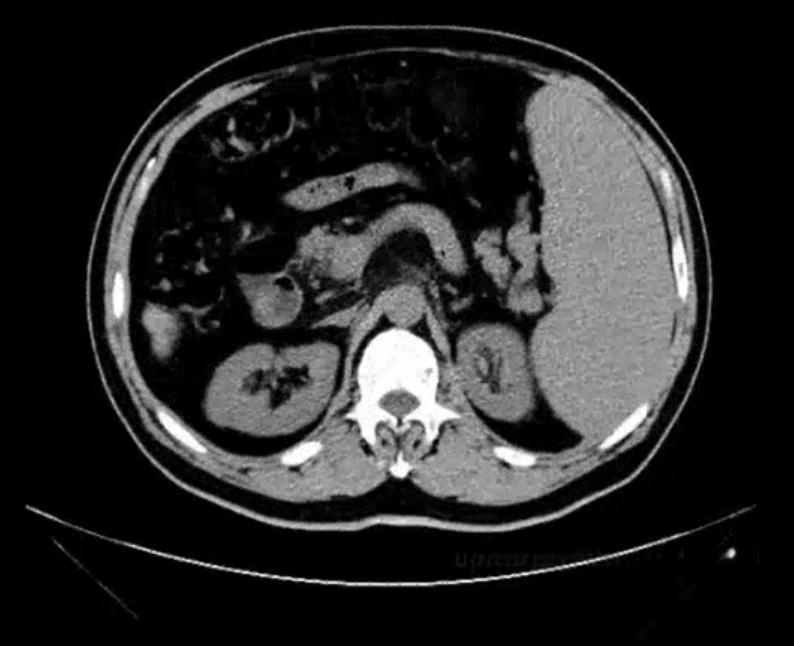

肝CT

- 40~60HU,高于胰,脾

- 肝内管道系统(胆管,肝动脉静脉和门静脉)低于实质,周围小分支多不显示。大血管呈低密度树状影

- CTA

正常肝重要结构